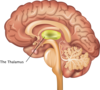

What components make up the Diencephalon?

Thalmus and Hypothalmus

What are the 3 components of the brainstem and the basic functions of each?

-

Midbrain (misencephalon)

- Eye movement and reflex responses to sound and vision

-

Pons

- Feeding and sleep (particularly REM)

-

Medulla

- Cardiovascular and respiratory centres

- Contrains major motor pathways (medullary pyramids)